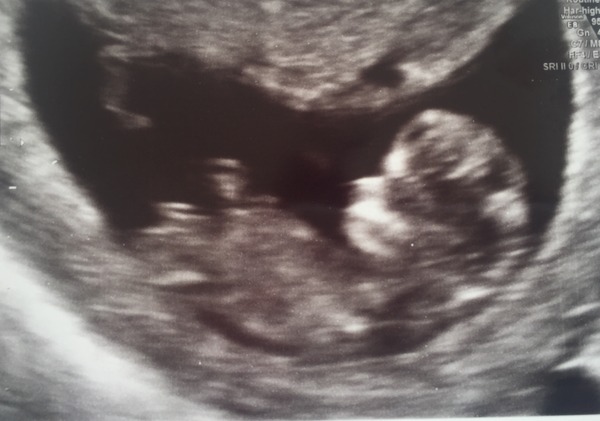

I survived my scan ladies with no coughing fit! We have one very wriggly baby with a good heartbeat! Grin it's still a bit small so for now they've estimated I'm 11+1, so asked me to go back in on the 12th for another scan to do the nuchal test and bloods. We're not going to find out the sex, but I love trying to guess. It's all become very real now!!

Congrats on the scan Teagirl! That's a really clear picture. Evs so glad you got the all clear in your tests.

Glad you've all had good scan appointments! Your photo is fab, teagirl!

teagirl lovely scan pic!

Teagirl - great picture! Well done on not having a coughing fit too. We will be scan buddies on the 12th!

Spots here too. Lovely scan tea.